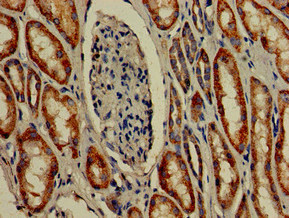

Immunohistochemistry of paraffin-embedded human kidney tissue using CSB-PA850263LA01HU at dilution of 1:100